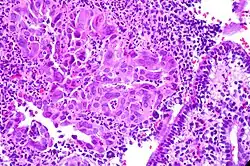

Die Zervizitis, Cervicitis (von Cervix für Gebärmutterhals) oder Gebärmutterhalsentzündung ist eine Entzündung des Gebärmutterhalses.[1][2]

Diagnose

Die Diagnose ergibt sich aus Kolposkopie mit Abstrich, der Infektionserreger kann mittels PCR oder HPV-DNA-Tests bestimmt werden.[1]